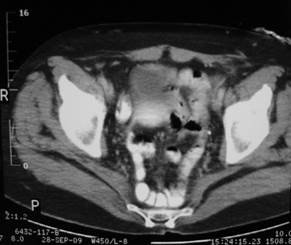

Figura 2. Caso 1: Tomografía computada donde se observa la hernia perineal y su contenido.

Figura 5. Caso 2: Tomografía computada. Corte sagital que muestra la hernia perineal.